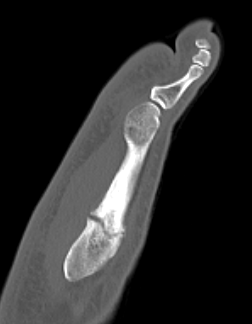

Intramedullary Screw

Screw fixation Zone 2 nonunion

Screw fixation Zone 3 nonunion

Technique

Entry point

- 5th metatarsal is not straight

- high and medial to get straight shot

- avoids plantar insertion peroneus brevis

- screw diameter 3.5 / 4.5 / 5.5 / 6.5

- screw threads must be distal to fracture site to allow compression